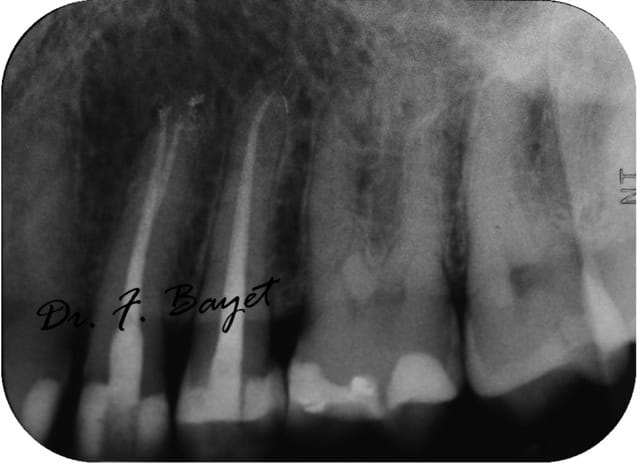

Exemple: sur une 38, cathétérisme au PathFile (violet, blanc, jaune) et WaveOne (toujours avec l'ATR), obturation systemB. Le crochet apical je l'ai découvert au moment de l'essayage des cônes !!

Img 0753  copie ugylxo - Eugenol

Img 0755  copie vongmr - Eugenol

Img 0759  copie tor4et - Eugenol